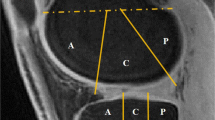

ASC measurements

Three regions-of-interest (ROI) of 40 pixels were drawn on the patellar (PAT), femorotibial lateral (LAT) and femorotibial medial (MED) cartilage, on eight consecutives slices of the ASC maps using the following protocol for each subject: (1) For each consecutive slice, draw a large ROI surrounding the cartilage area where we want to make the measurement; (2) On the first R3D data (baseline), select 40 pixels with highest ASC values within the large ROI; (3) Generate a mask from this 40-pixel area; (4) Transpose this mask to all other three co-registered datasets (baseline IRW, follow-up R3D and follow-up IRW); (5) Measure the pixels values corresponding to the mask in each dataset; (6) Calculate the mean and standard deviation (std) of ASC over all 320 pixels (eight ROIs of 40 pixels). Examples of ROIs and masks to measure ASC values in PAT (transverse slice), MED and LAT (coronal slice) are shown in Fig. 1. This procedure ensures that all the ASC values are measured at exactly the same locations in all 3D sodium datasets for each subject.

Examples of large regions-of-interest (ROIs) and masks generated from 40 pixels with the highest values within the large ROIs, on a transverse slice showing patellar cartilage (PAT), and on a coronal slice showing femorotibial lateral (LAT) and medial (MED) cartilage. These large ROIs and masks are generated on the first dataset acquired on each subject (R3D at baseline). These masks are then transposed to the three other co-registered datasets (baseline R3D, follow-up R3D, follow-up IRW) where all 40 corresponding pixel values are measured. This procedure ensures that all the ASC values are measured at exactly the same locations in all 3D sodium datasets for each subject